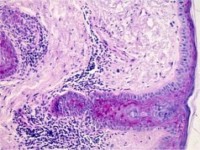

PA:De epidermis

is niet aangedaan. In de dermis, zowel oppervlakkig als diep is er sprake van

een dicht infiltraat van kleine, normaal uitziende lymfocyten rond de bloedvaten

en adnexen. De infiltraten zijn nodulair en hebben een scherpe overgang naar

de normale aangrenzende dermis. Immunohistochemisch wordt voornamelijk een infiltraat

gezien van CD8+ T-lymfocyten, hoewel ook CD4+ T-lymfocyten kunnen worden gezien.

Verder is er een licht verhoogde hoeveelheid mucine in de reticulaire dermis.

Vacuolisatie van de basale membraan en folliculaire plugging worden niet gezien.

IF (lupus band) is negatief. Als er histologisch een dicht lymfocytair infiltraat